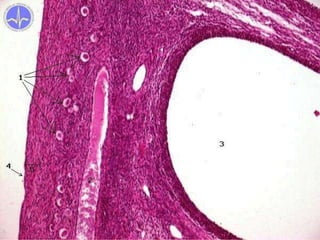

Folliculi ovaricia maturi

Matured follicles (Graafian)

• 2-2,5 cm

• oocyte located peripherally (cumulus

oophorus) and adjacent granulosa forms

corona radiata

• protrudes on surface (stigma folliculare)

• thinned capsule and suppressed blood supply

• rapid increase of LH blood level causes

rupture of follicle

• finishes 1st meiotic division and

continues to the 2nd → secondary oocyte

• oocyte and corona radiate are released